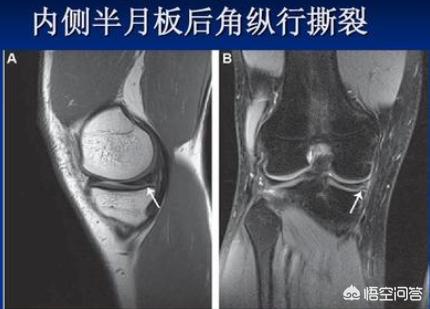

您可以看一下下方的图片,是不是这个位置的疼痛,因为您表述的不是特别清晰,因为前几天我刚巧回答过一个类似问题。

如果您是这个位置的疼痛,伴有蹲起时候的无力疼痛等情况,最大的可能性膝关节内侧半月板损伤。

半月板是我们关节内的一个非常重要的结构,就类似我们家水龙头里面的胶皮垫子一样,起到了很好地帮助缓冲的作用,同时参与关节的屈伸运动,匹配关节的功能,在膝关节内的地位十分重要。在我们的关节内有两个这样的半月板,分别称为内、外侧半月板。

内侧半月板撕裂会造成内侧关节间隙的疼痛,不能正常蹲起,严重时会诱发反复的积液,患者特别痛苦。外侧半月板撕裂的主要症状是下楼梯时候的疼痛,关节不敢正常伸直,否则诱发剧烈的关节疼痛,睡眠时有的患者都需要屈膝才能减轻疼痛。

您的这种情况就不排除是否是内侧半月板损伤,那么应该怎么办呢?您应该做一个膝关节的核磁,半月板属于关节软骨,普通X光或者CT根本无法看到半月板的形态以及细节,只有核磁才能精确地显示半月板的结构以及是否损伤,同时可以观察关节内的软骨是否存在问题,关节内是否有少量积液等等细节。

我想您已经疼痛一年了,如果还没检查核磁的话,现在赶紧去检查一下吧,一般的医院核磁468元左右,赶紧明确问题,抓紧时间治疗。

确定是半月板损伤的话,如果是1、2度的半月板损伤,我们可以采取保守治疗,比如口服药物,比如关节内注射玻璃酸钠,这都是很好的治疗方式。如果是三度半月板损伤的话,可能需要关节镜的手术治疗,这是一种微创的手术,可以很好的帮助我们治疗半月板的损伤,但是前提一定是要有一个核磁,明确半月板损伤达到了什么程度,是否需要手术。